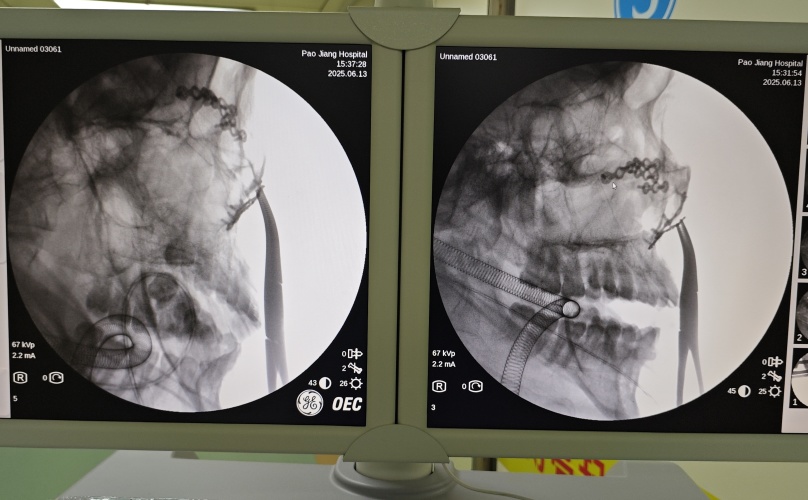

我院迅速为患者安排手术,由特邀专家王艳主任带领团队在全麻下行左侧颧骨及上颌骨骨折切开复位内固定术。手术团队采用冠状切口(发际后15cm)联合口腔前庭切口(3-4cm)双入路,精细分离暴露骨折部位。

术中发现颧骨体多发骨折伴内下移位,上颌窦外侧壁骨折伴游离骨片。以解剖标志为导向精准复位后,植入钛板及数枚螺钉固定。

术中特别注意保护眶下神经、上牙槽神经等重要结构,通过咬合关系评估和面部对称性检查确认复位效果。手术顺利结束,患者转入病房,医护人员为其密切观察伤口情况。